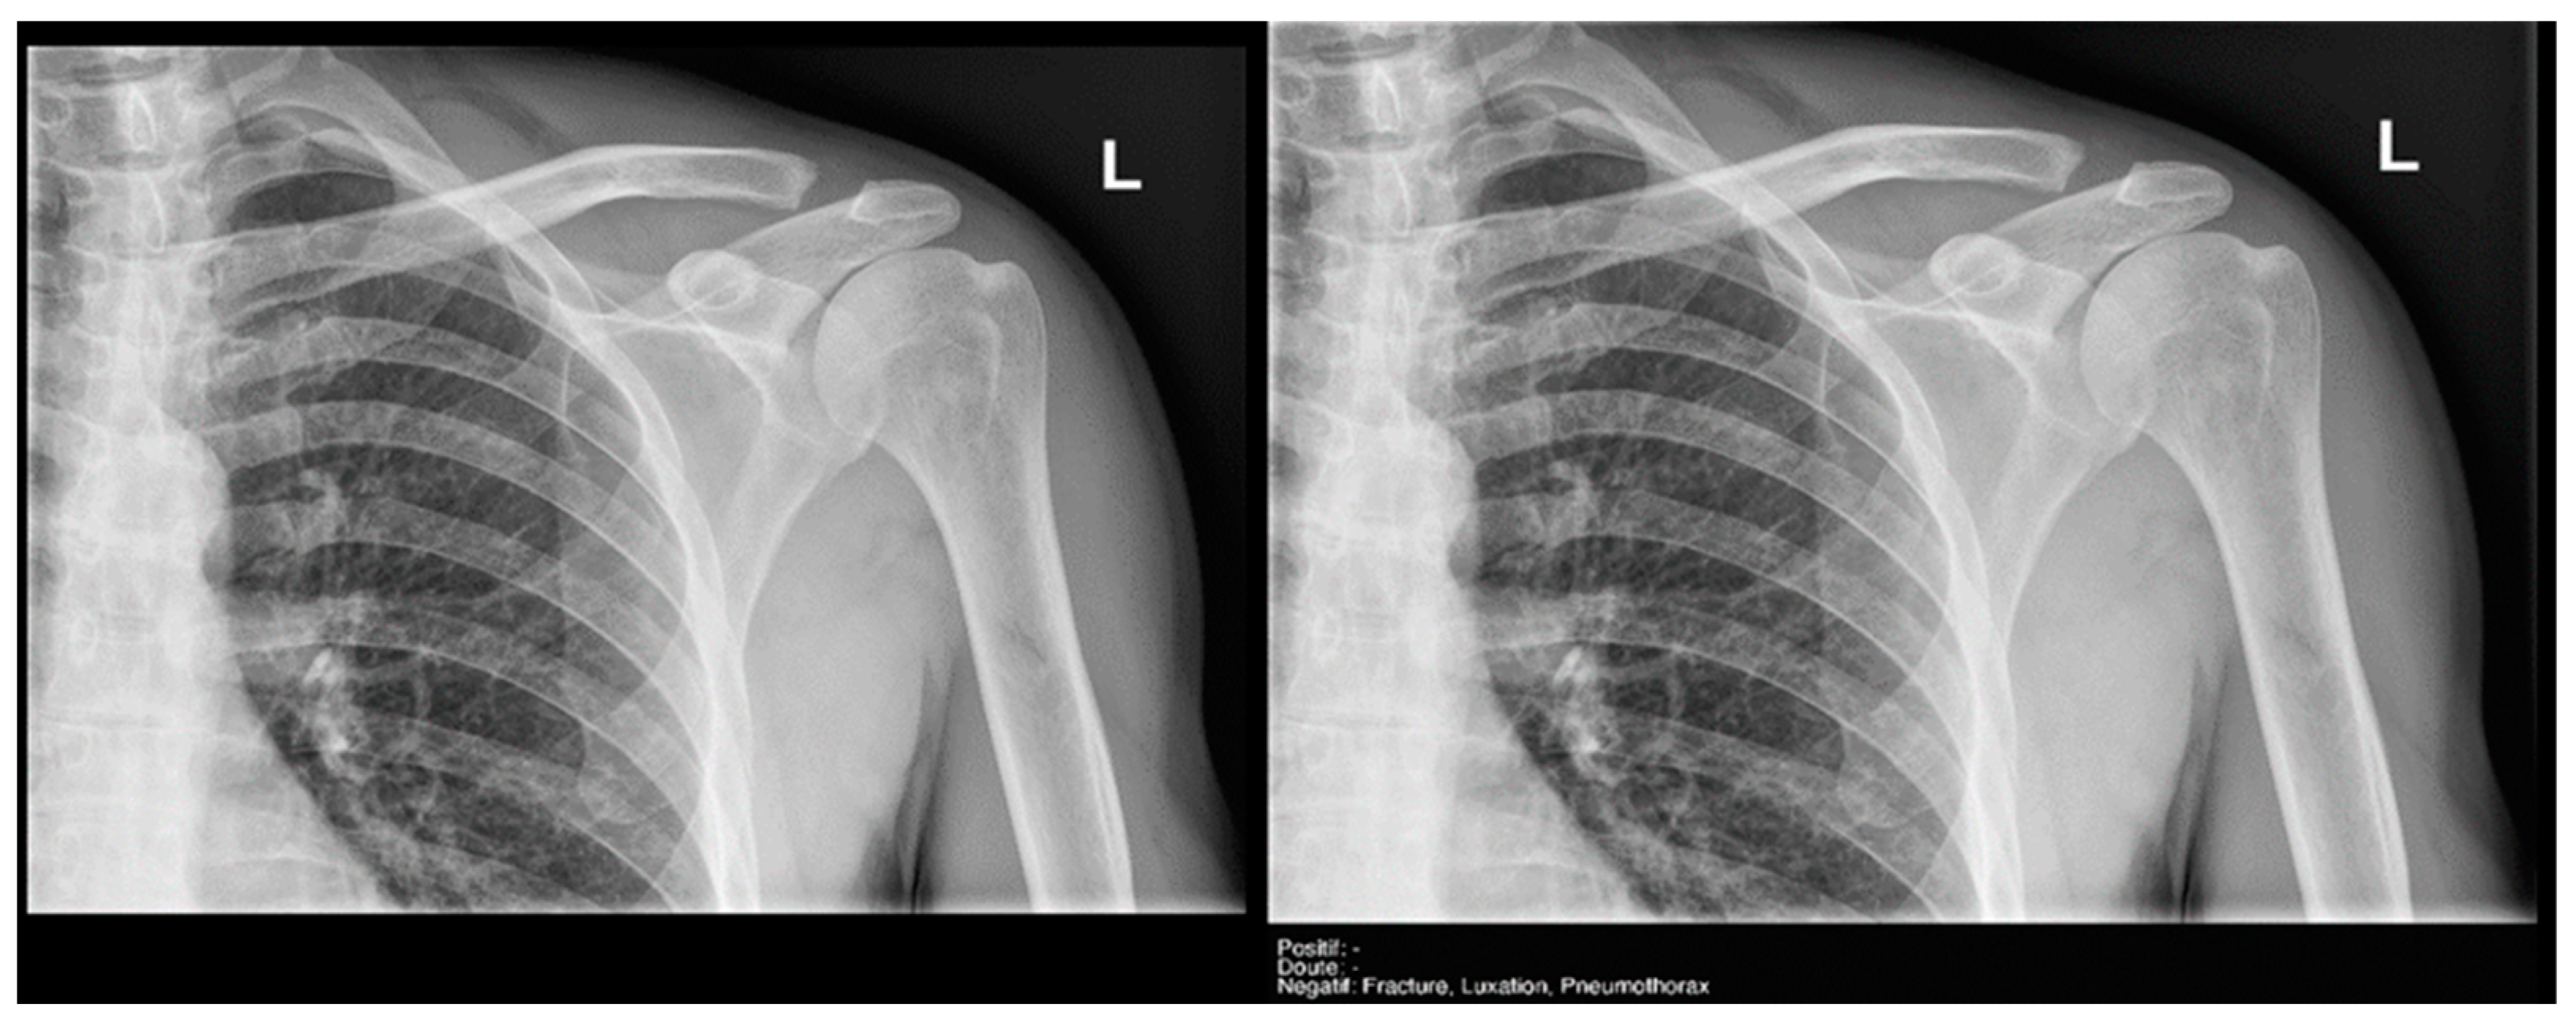

3.3.2. Acute Joint Dislocation